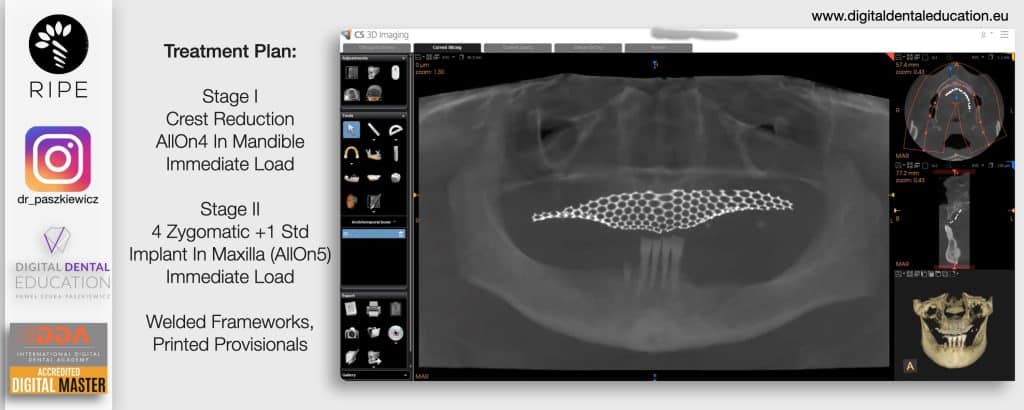

He has invented an AllonX non-impression protocol leading to final restorations post immediate implant full-arch loading, incorporated with desktop scanner (MEDIT) and ModJaw capturing of natural patient’s functional and mastication movements.